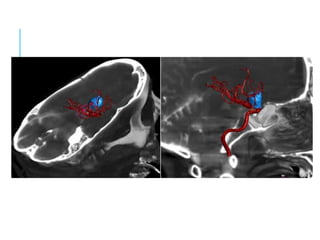

APLICACIÓN 3D

Proceso computacional mediante el cual es posible

provecho diagnóstico y terapéutico.

ANGIOGRAFÍA 3D

La información, es obtenida porque durante la

adquisición el equipo realiza un movimiento de 240º

en 4 segundos.

Formando una imagen muy similar a las entregadas

por un TAC o RNM.

A esto se le llama ANGIOGRAFÍA ROTACIONAL

TRIDIMENSIONAL.

La imagen es realizada en forma instantánea.

Tiene gran utilidad en las imágenes de Aneurismas,

MAV cerebrales, como así también de ACV.

APLICACIÓN 3D Proceso computacionalmediante el cual es posible reconstruir en forma tridemensional una imagen vascular, a partir de la adquisición radiológica de datos durante una angiografía, logrando mediante un software de aplicaciones la manipulación de tales datos para el provecho diagnóstico y terapéutico.

ANGIOGRAFÍA 3D La información,es obtenida porque durante la adquisición el equipo realiza un movimiento de 240º en 4 segundos. Formando una imagen muy similar a las entregadas por un TAC o RNM. A esto se le llama ANGIOGRAFÍA ROTACIONAL TRIDIMENSIONAL. La imagen es realizada en forma instantánea. Tiene gran utilidad en las imágenes de Aneurismas, MAV cerebrales, como así también de ACV.